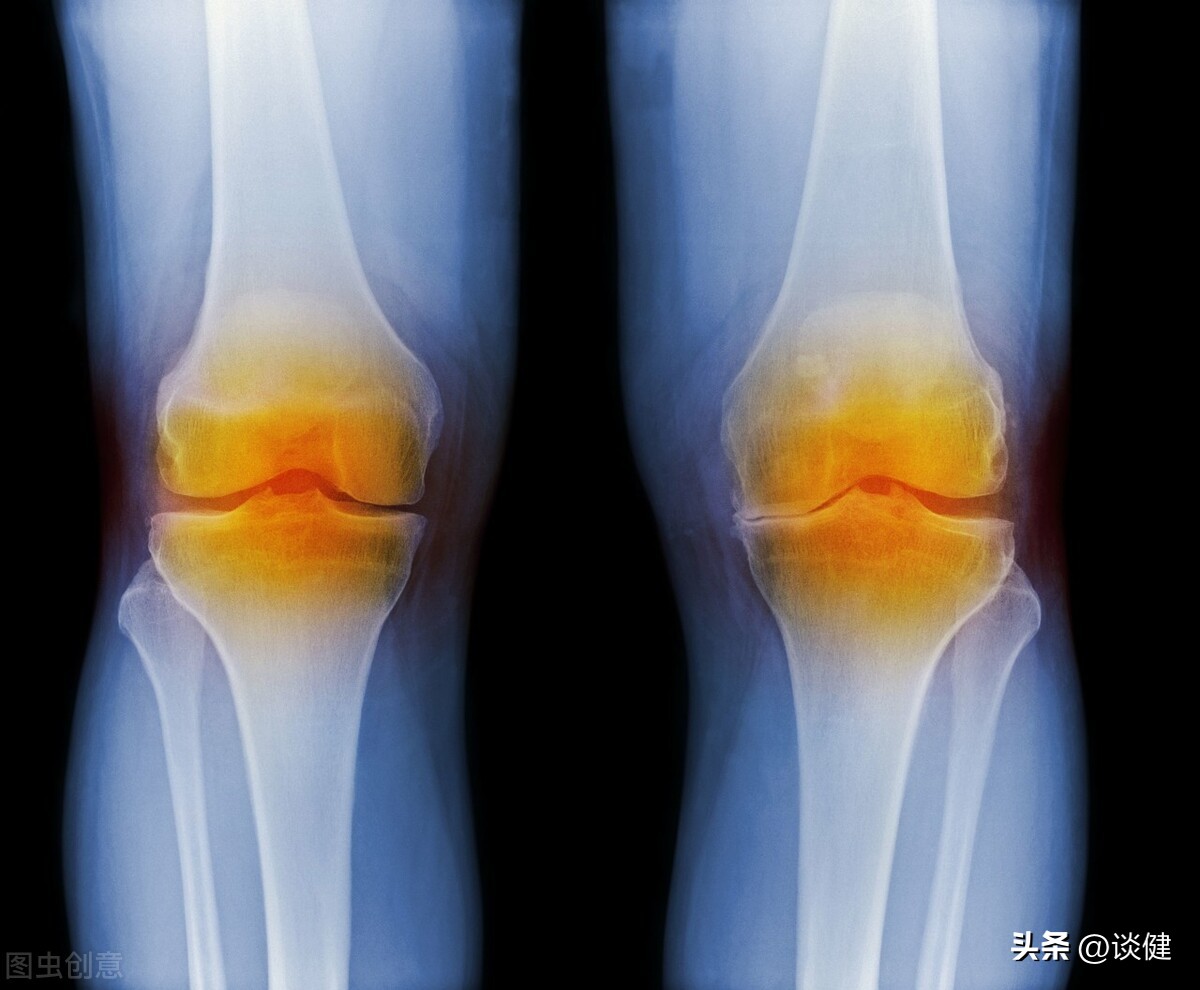

膝关节是由股骨(大腿骨)、髌骨、前后十字韧带、软骨及胫骨所组成。髌骨是浮在股骨与小腿骨上方一块三角形状的小型骨头,藉由卡在股骨上的凹槽里,提供膝盖活动时的稳定性,并藉由上下左右的各方拉力连结,使人体能做出各种走、跑、跳、蹲的动作。前后十字韧带连接股骨与胫骨,有稳定膝关节的作用,可以防止胫骨过度移位。至于胫骨上端膨大,上有软骨,左右各有一半月板,可吸收关节活动的压力。

退化性关节炎是中老年人常见的疾病。它是因为关节经年累月使用,或外来因素破坏,导致原本光滑的关节软骨产生屑片脱落,而出现发炎、疼痛的现象。退化性关节炎经常是中老年人冷风下的恶煞。大部分的人在初期时并不特别在意,认为老之将至罢了。医师强调,退化性关节炎不但使患者生活在疼痛中,更可能使行动变得不自如,因而应对此症多一分关心。 退化性关节炎早期并无明显症状,所以很容易被人忽略。因此,如果您是50岁以上银发族、肥胖的中年人(尤其妇女)、骨质疏松患者及有此症家族史的人,一旦出现关节僵硬、肿胀、疼痛等现象时,一定要速至医院检查、治疗,以免病情日益加重,或演变成慢性病,使行动受到限制。